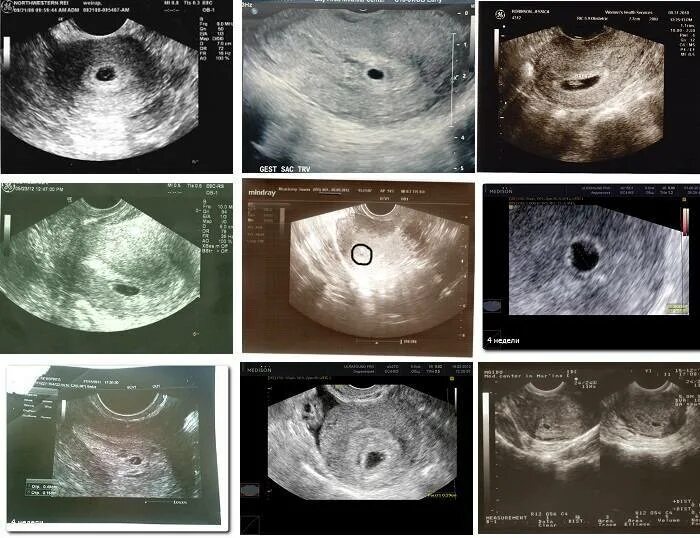

Эмбрион 4 недели 4 дня